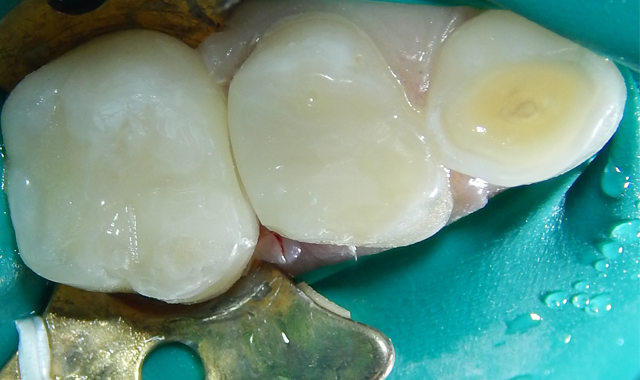

Following gross carious dentin removal, the pulps were not exposed but a pinking blush was noticeable. Following debris removal by copious rinsing, the enamel margins were etched with UNI-ETCH® w/ BAC (BISCO). The dentin was etched to remove the smear layer but not widen the dentinal tubules (Figs. 4-5).

Fig. 4 Fig. 5